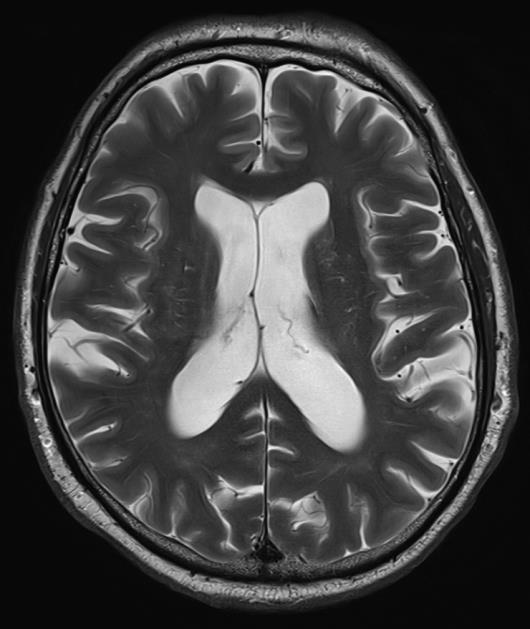

Conventional Deep Resolve

Deep Resolve is our AI-powered image reconstruction technology for MRI

• Enabling faster acquisitions, increased clinical productivity and better patient experience

• Increased image quality and resolution

• Reduced energy consumption per acquisition 2x